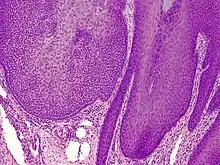

Trichilemmoma (also known as "tricholemmoma"[1]) is a benign cutaneous neoplasm that shows differentiation toward cells of the outer root sheath.[2]: 673 [3] The lesion is often seen in the face and neck region. Multifocal occurrence is associated with Cowden syndrome, in which hamartomatous intestinal polyposis is seen in conjunction with multiple tricholemmoma lesions.

A trichilemmoma on a forehead